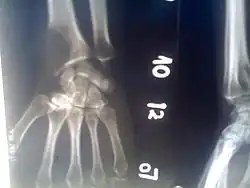

Osteolytic lesion

An osteolytic lesion (from the Greek words for "bone" (ὀστέον), and "to unbind" (λύειν)) is a softened section of a patient's bone formed as a symptom of specific diseases, including breast cancer and multiple myeloma. This softened area appears as a hole on X-ray scans due to decreased bone density, although many other diseases are associated with this symptom.[1] Osteolytic lesions can cause pain, increased risk of bone fracture, and spinal cord compression.[2] These lesions can be treated using bisphosphonates or radiation, though new solutions are being tested in clinical trials.